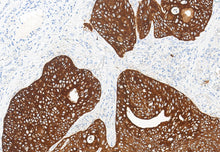

Cytokératine (Pan)

Localisation : Cytoplasme

CK Pan (pan-cytokératine) est une kératine intermédiaire épithéliale typique, largement exprimée dans la majorité des cellules épithéliales et leurs tumeurs dérivées.

Elle réagit positivement dans presque tous les carcinomes (adénocarcinomes, carcinomes épidermoïdes, carcinomes urothéliaux, etc.) mais pas dans les tumeurs non épithéliales comme les sarcomes, lymphomes et mélanomes.

Le motif de coloration cytoplasmique est très spécifique, faisant de CK Pan un marqueur fondamental et essentiel en pathologie.

Contrôle positif : Tissu de carcinome épidermoïde pulmonaire